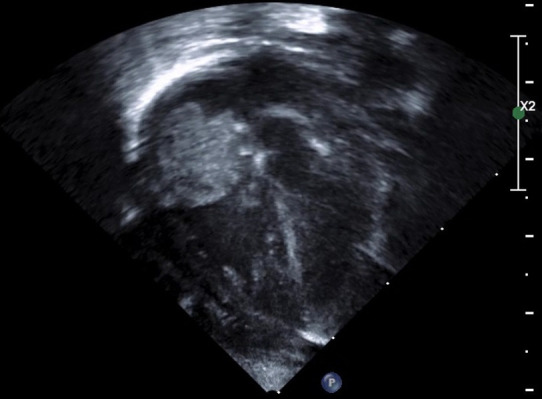

Infective atrial thrombus.